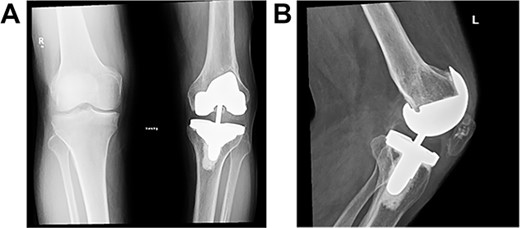

At the 2-year follow-up visit, the patient’s active ROM continued to be between 4 and 85° (Fig. 7). Patient’s functional outcome score was measured using the Knee Injury and Osteoarthritis Outcome Score pre- and post-operatively, with marked improvement in scores noted from 45 to 76%.

Post-operative plain radiographs at 2-year follow-up visit; (A) 2-year post-operative AP radiograph showing implant in place with decreased lateral gap sized to be 1.57; (B) 2-year post-operative lateral radiograph of the knee showing implant in a satisfactory position.